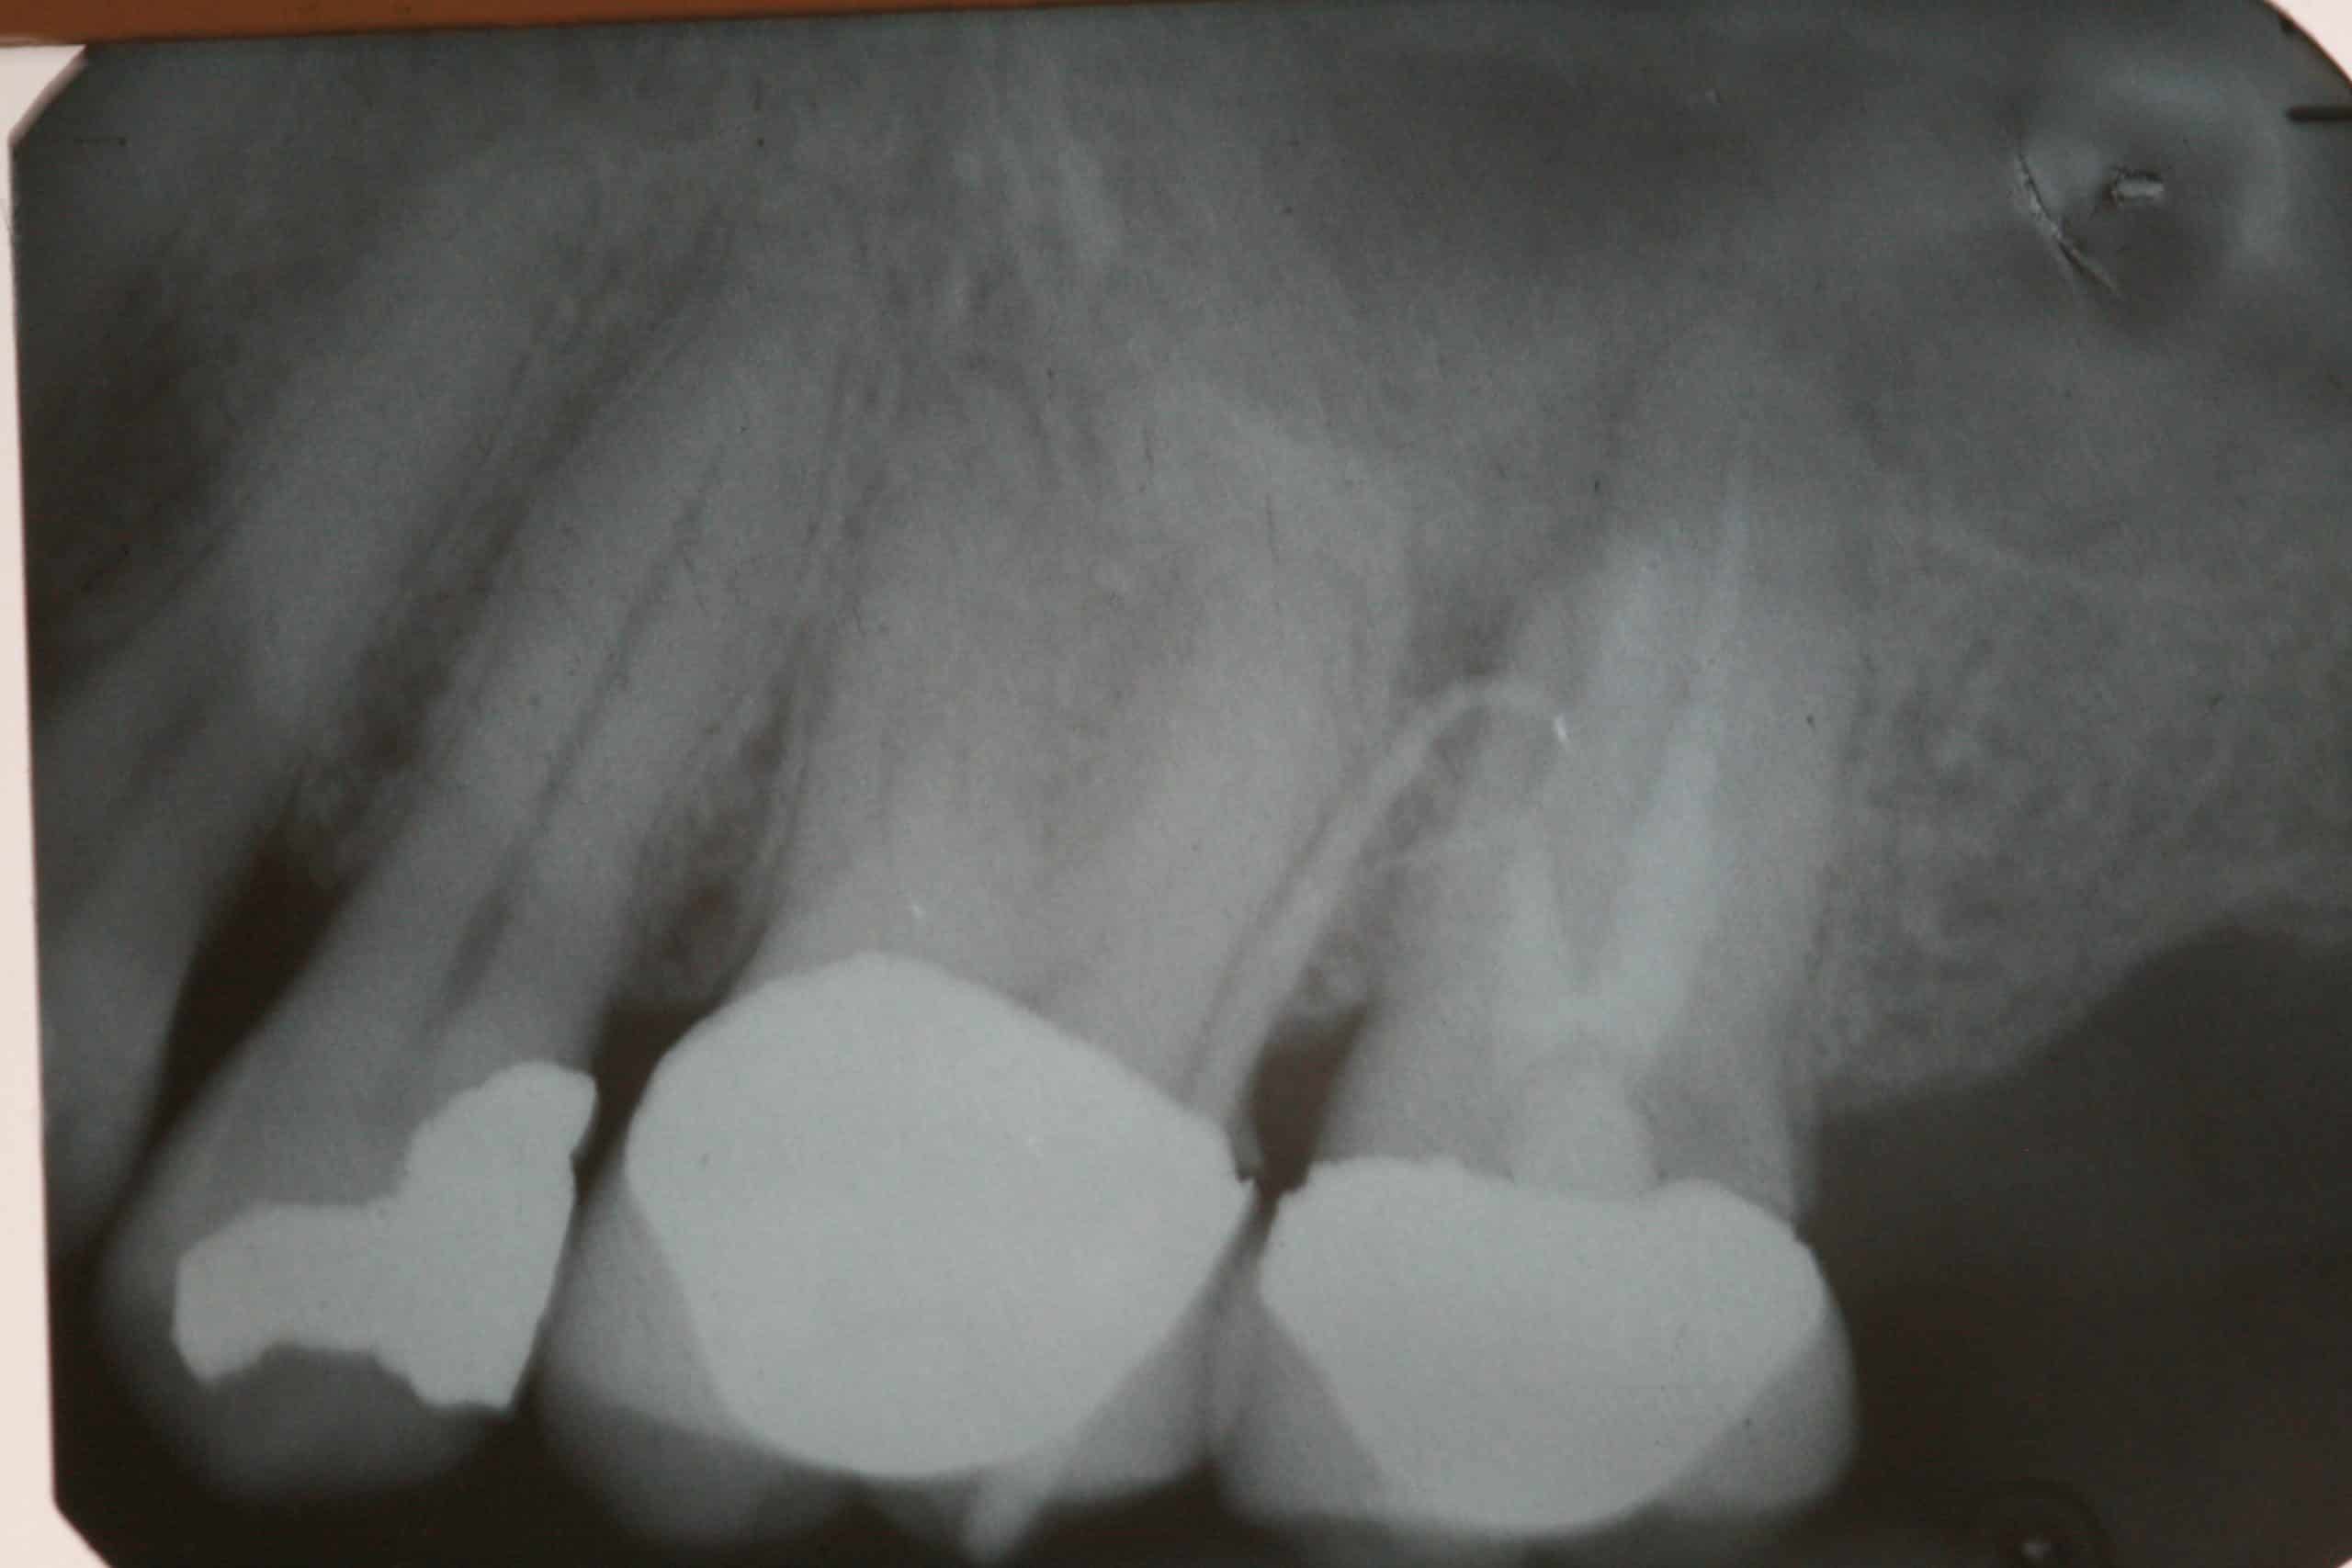

Oral Fistula Traced Advanced Dentistry & Dental Implant Center What Is Dental Fistula Learn how to identify, treat, and prevent this oral health. A dental fistula is a small tunnel that drains pus from an infected tooth or gum. A dental fistula is an abnormal channel that transports fluids, such as pus, from an area of inflammation to the exterior. Learn about the potential causes, recognizable symptoms, and. Learn how to recognize the. What Is Dental Fistula.

EndoResto molar inferior con fístula Formación Clínica Dental Esteve What Is Dental Fistula Learn how to identify, treat, and prevent this. A dental fistula is a new pathway that drains infection from an abscess under the gumline. Learn how to recognize the. A dental fistula is a drainage pathway that connects a dental abscess with the outside. A dental fistula is an abnormal channel that transports fluids, such as pus, from an area. What Is Dental Fistula.